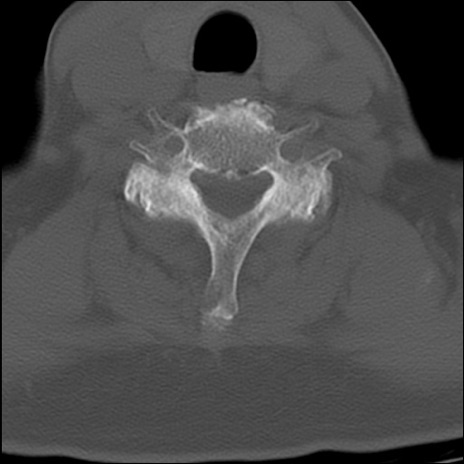

症例48 頚椎CT(横断像)

頚椎CT